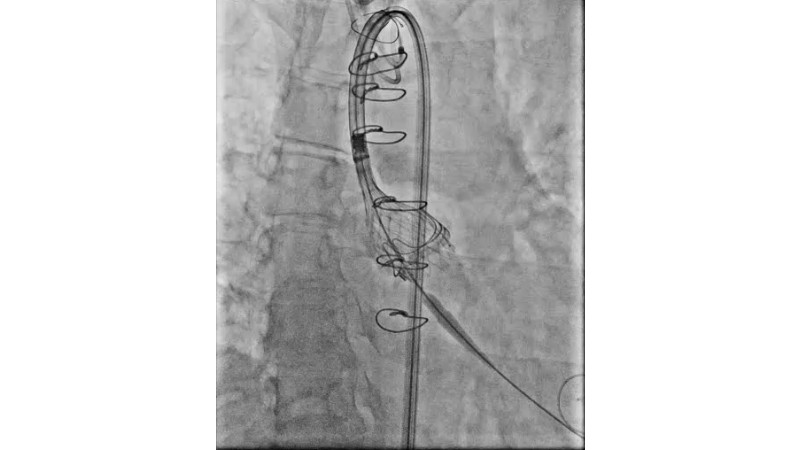

This session explores the evolving landscape of transcatheter aortic valve implantation (TAVI) with a focus on supra-annular valve technology. It covers techniques for achieving commissural alignment, considerations for small aortic annuli, and advantages in treating bicuspid aortic valve disease, supported by clinical data and illustrative cases.

- To learn how to perform TAVI resulting in commissural alignment and easier coronary access